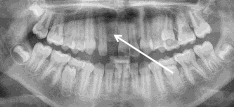

Een grotemensentand (of -kies) kan je missen doordat deze verloren is gegaan door tandheelkundige problemen in of rondom die tand of ten gevolge van een ongeval. Echter, meestal komt dit doordat één of meer van die tanden nooit zijn aangelegd; dit komt voor bij 5% van de mensen.